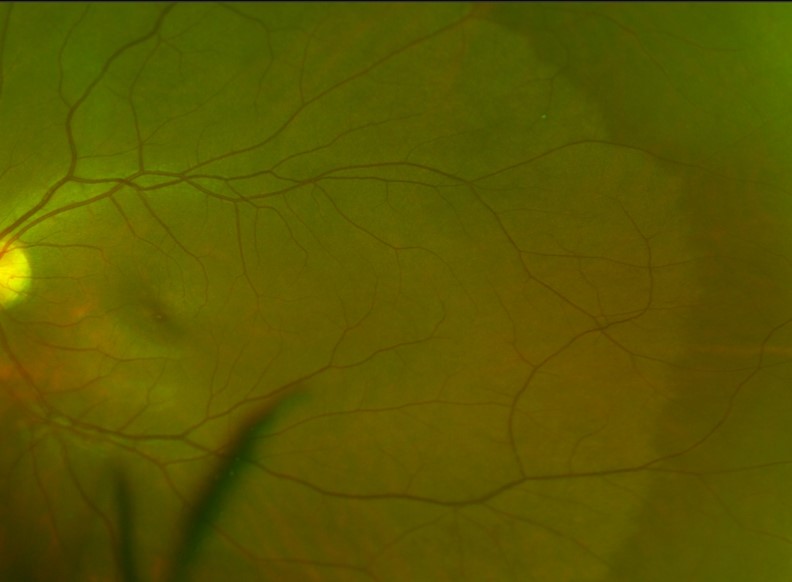

Dark without pressure (DWOP) is most commonly found in darkly pigmented retinas. It presents as a flat, dark patch of the retina with well defined, sometime scalloped borders. Similar to WWOP it can change over time. DWOP has hypo-reflective changes in the same layers as WWOP.

A 29-year-old asymptomatic Asian male with best corrected visual acuity of 6/6 (20/20) in the left eye.

A 28-year-old asymptomatic Asian female with best corrected visual acuity in each eye of 6/6 (20/20).